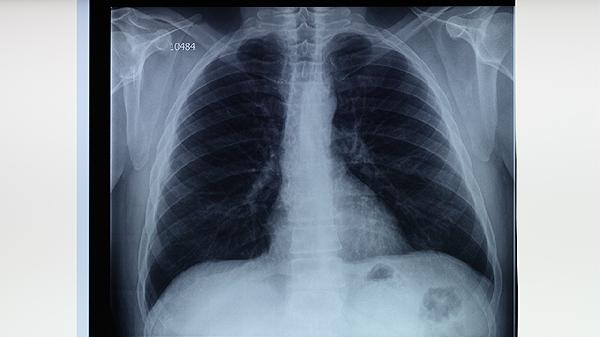

肺结核通过规范治疗可以治愈,疗程通常需要6-9个月,活动性肺结核患者需隔离至痰菌转阴。肺结核的治疗与隔离措施主要与病情分期、药物敏感性、传染性控制等因素相关。

初治肺结核标准疗程为6个月,前2个月为强化期使用四种药物联合治疗,后4个月为巩固期使用两种药物。复治或耐药结核患者疗程延长至9-24个月,具体时间取决于细菌学检查结果和影像学改善情况。

痰涂片阳性的活动性肺结核患者需进行呼吸道隔离,隔离期一般为2-4周直至连续3次痰菌检查阴性。密切接触者需进行结核菌素试验筛查,儿童、老年人等易感人群可预防性服用异烟肼。